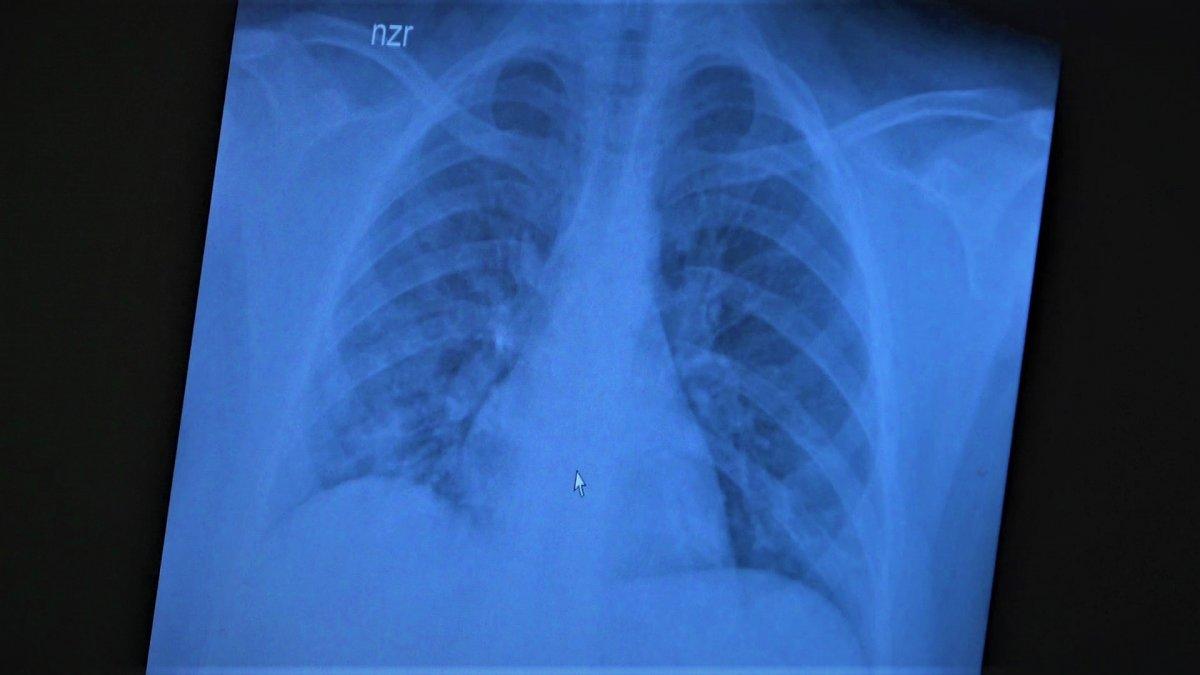

Çocukların akciğer tomografilerini inceleyen Özkaya, açıklamalarına şu ifadeler ile devam etti:

“11 yaşında kovid pozitif bir öğrencimiz, yüksek ateş ve nefes darlığı ile bize geldi. Ciddi akciğer tutulumu var. Geçen yıl ‘bu çocuklar hastalıktan etkilenmiyor’ diyorduk. Bu çocukta görüyorsunuz buzlu camlar ve konsolidasyon alanlarla seyrediyor. Geçen yıl bu şekilde çok çocuk görmüyorduk. Önümüzdeki aylarda bu şekilde devam ederse çocuklarımızı kaybetmeye bile başlayabiliriz.